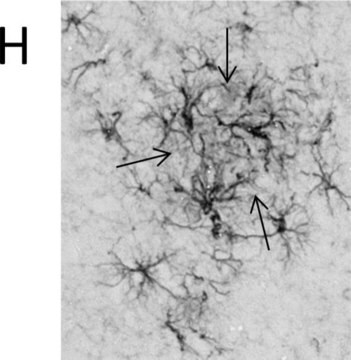

小鼠胶质纤维酸性蛋白(GFAP)单克隆抗体适合以1:400的工作稀释度用于大鼠脑切片(酒精固定)的免疫组织化学分析以及微阵列分析。它可用于人、猪和大鼠组织中GFAP的免疫细胞化学定位。它也适用于通过免疫印迹测定法定位GFAP。在对酒精固定或冷冻切片进行间接免疫荧光标记时,可使用该抗体对星形胶质细胞和Bergmann胶质细胞、胶质瘤和其他神经胶质细胞衍生肿瘤进行染色。

该抗体在免疫印迹分析中可与GFAP发生特异性反应,在免疫组织化学染色中可标记星形胶质细胞、Bergmann胶质细胞和弹性软骨的软骨细胞。抗体与冷冻或酒精固定组织切片中的胶质细胞特异性抗原反应。